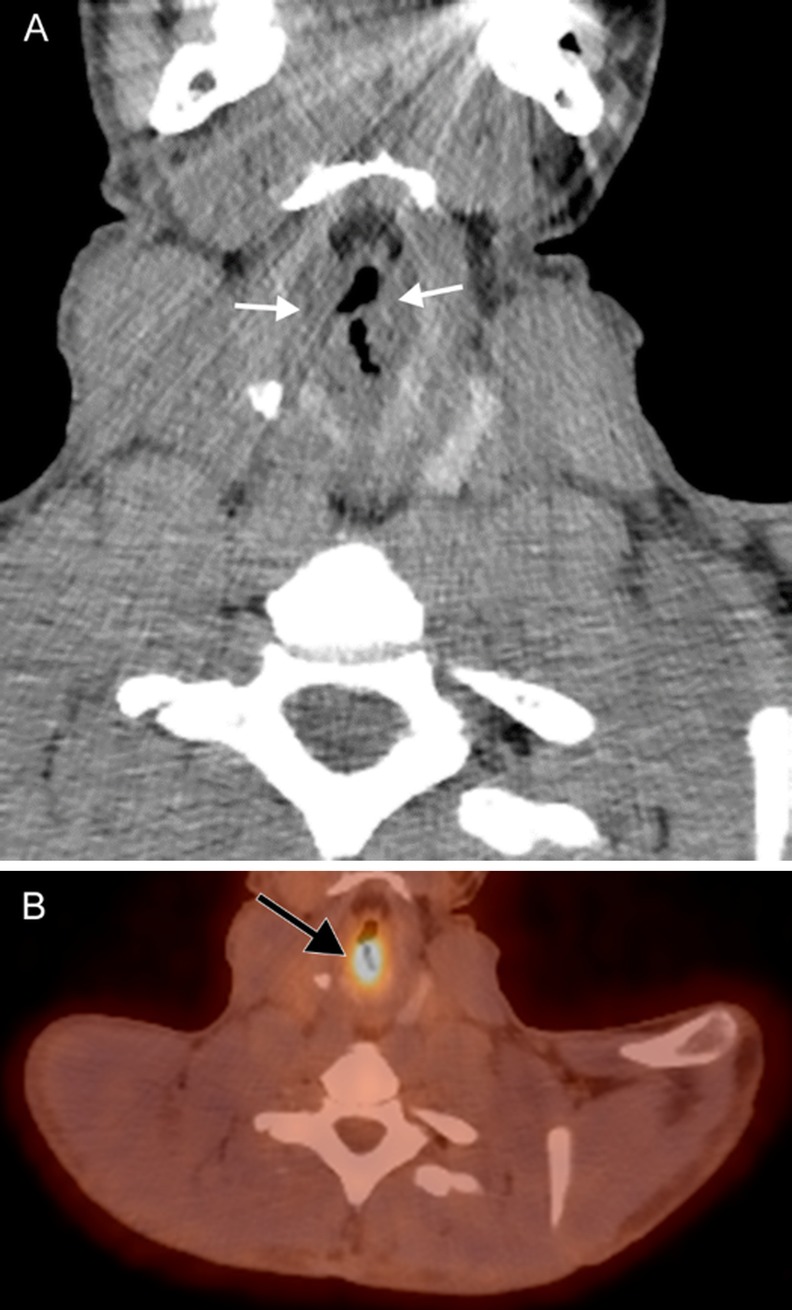

Fig. 8.

Laryngeal papillomatosis. A 26-year-old man with recurrent tracheal/laryngeal papillomatosis status post tracheal diversion and radiation therapy. A coronal contrast-enhanced CT image (a) reveals nodular soft tissue attenuation (white arrows) replacing the laryngeal structures. Subsequent axial attenuation-corrected PET image (b) reveals marked FDG-avidity (black arrow)